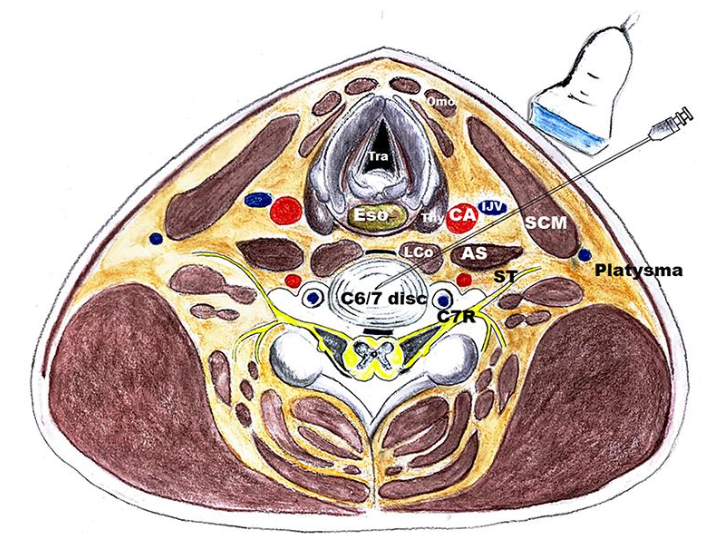

5. Ultrasound-Guided Trigger Point Injections

Mechanism of Action

- Deactivates taut muscle bands

- Restores muscle length and circulation

Indications

- Myofascial pain syndrome

- Postural neck pain

- Office-related neck pain

Contraindications

- Bleeding disorders

- Needle phobia (relative)